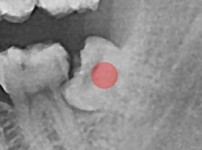

부분 매복 사랑니